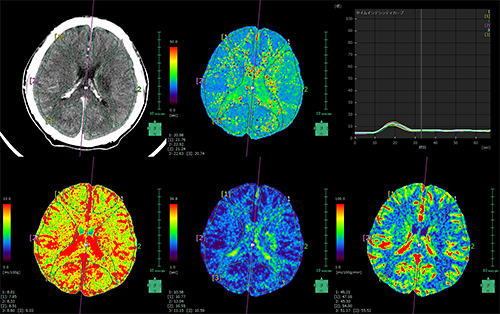

パフュージョン(CT/MRI)

CT・MRIで撮影された同一断面のダイナミックスキャン画像から、脳血流の動態を解析し、CBV(脳血液量)、CBF(脳血流量)、MTT(平均通過時間)、TTP(造影剤の到達ピーク時刻)を算出します。

4Dパフュージョン

全脳CTのダイナミック画像を用いて、脳血流情報を測定できます。脳表抽出や骨・動静脈抽出にも対応しており、3Dや4D画像とのフュージョンも可能です。